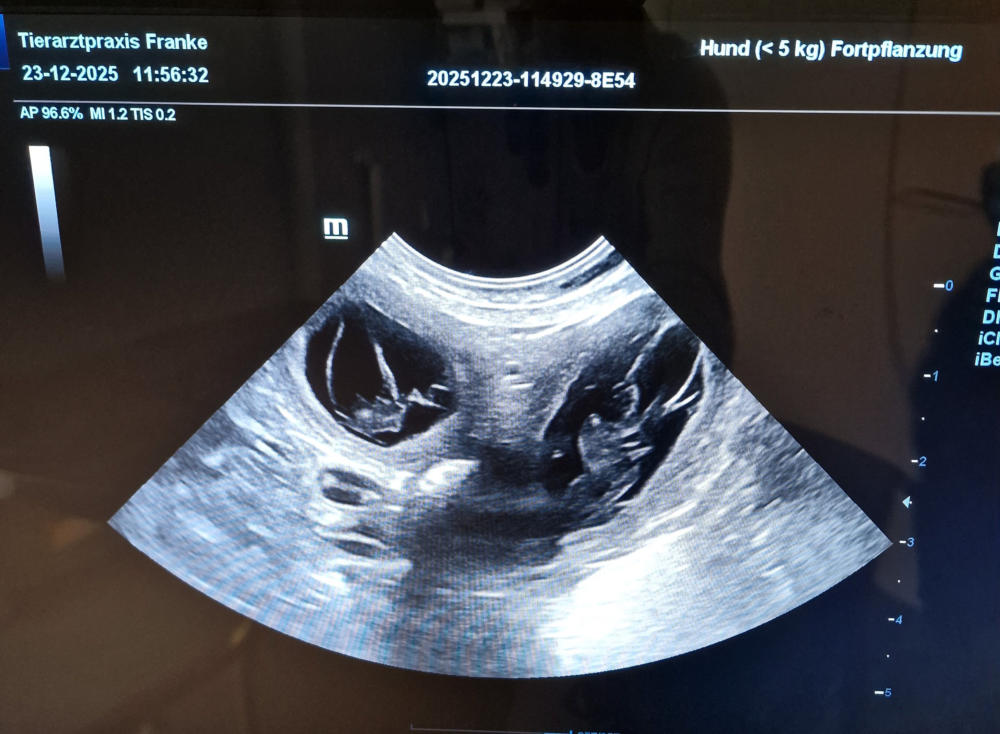

Unsere süße Pia hatte Ende November ein Date mit unserem Charmeur Luis. Der Ultraschall am 23.12.2025 hat es bestätigt. Wir freuen uns sehr, dass kleine Herzchen in Pia schlagen.

Bevor wir in den nächsten Tagen unsere Babys „life“ sehen können, waren wir heute nochmal bei der Tier- ärztin und haben „Bildchen geguckt“. Die Kleinen sind kräftig und gut entwickelt, so dass wir jeden Tag auf das kleine Wunder warten können. Das Welpen-Nestchen ist vorbereitet, die Geburtsutensilien liegen bereit und nun wird es in den nächsten Tagen spannend… Wir freuen uns riesig!